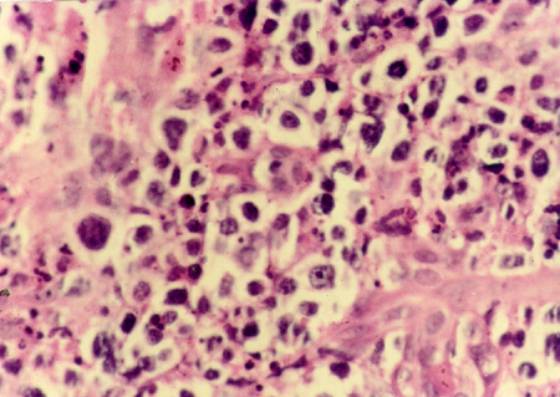

3. 组织病理示坏死性肉芽肿改变,血管壁受累,免疫病理证实主要为T细胞浸润、增生。